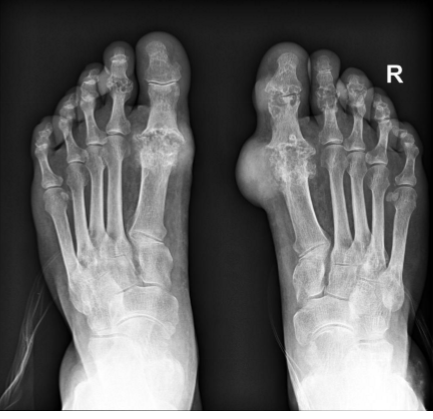

radiology - gout

most often affects the metatarsal-phalangeal joint of the great toe with the juxta-articular erosions and/or little to no osteoporosis

tophi = late manifestations of the disease